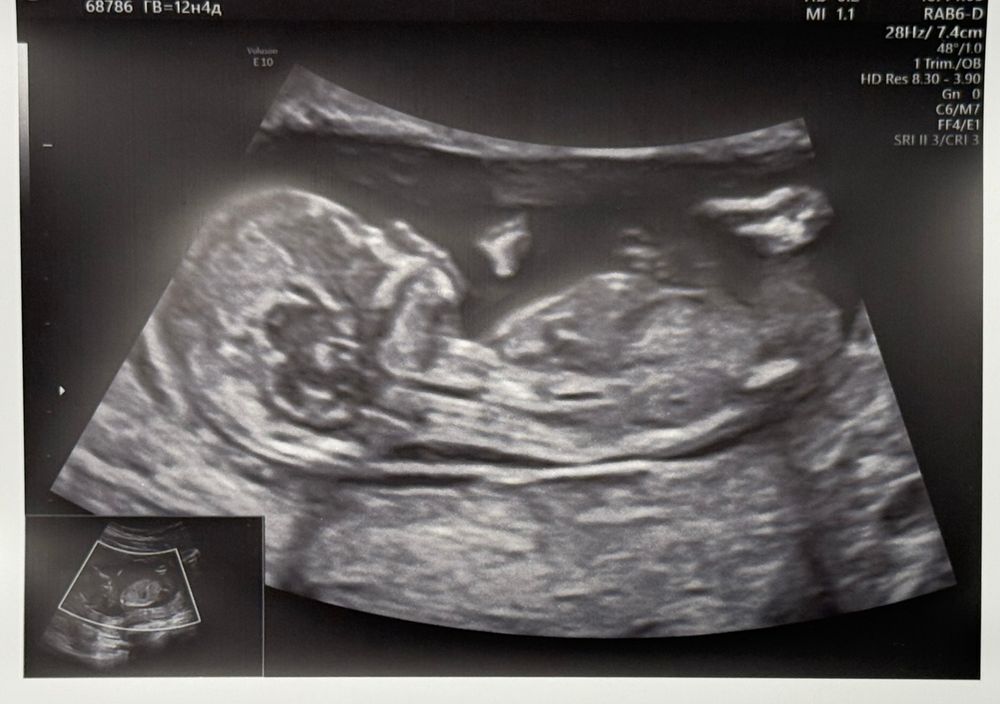

Половой бугорок (пол девочка или мальчик) 12 недель

Не видно бугорок.

на втором фото девочка похоже

А у врача не спросили? На втором фото не видно, на первом, если правильно его распознала, то девочка)

А мне кажется что девочка.)))

я в этом не понимаю, но мне каж мальчик)))

Мальчишка 😀